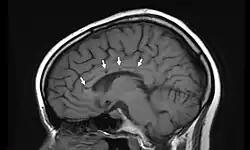

| Sagittal T1 image in a 19-year-old woman with Susac's syndrome showing the pathognomonic central callosal "holes" (microinfarcts) of SS. These residual "holes" (and sometimes, "spokes") develop as the acute callosal changes resolve. | |

In a recent analysis (Susac et al., 2003), MRI images from 27 patients fulfilling the diagnostic criteria of Susac's syndrome were reviewed. Multifocal supratentorial lesions were present in all patients. Most lesions were small (3 to 7 mm), though some were larger than 7 mm. All 27 patients had corpus callosum lesions. These all had a punched-out appearance on follow-up MRI. Though most commonly involving white matter, many patients also had lesions in deep grey matter structures, as well as leptomeningeal enhancement. Multiple sclerosis (MS) and acute disseminated encephalomyelitis (ADEM) can mimic the MRI changes seen in patients with Susac's syndrome. However, the callosal lesions in Susac's syndrome are centrally located. In comparison, patients with MS and ADEM typically have lesions involving the undersurface of the corpus callosum. Deep gray matter involvement commonly occurs in ADEM but is very rare in MS. Leptomeningeal involvement is not typical of either MS or ADEM: if 10 lesions are found in the brain of an MS patient, a lesion may be found in the corpus callosum. If a Susac patient has 10 lesions, more than half will be in the corpus callosum.